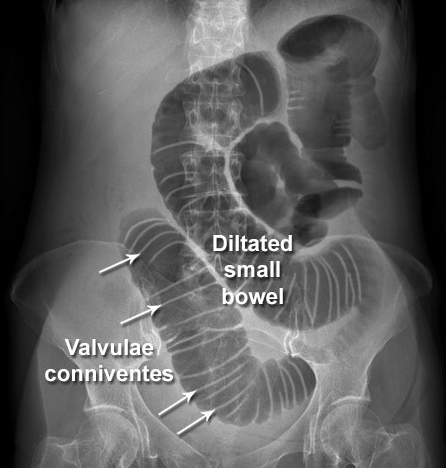

24-year-old patient with suspected appendicitis. What does the image show?

Small bowel obstruction

Dilated loops of bowel with valvulae conniventes – lines crossing the full width of the bowel – indicates small bowel obstruction.